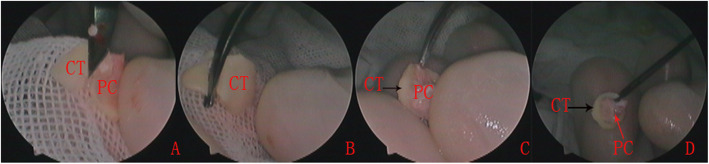

In the double layer cartilage-perichondrium group, tragal cartilage with a single layer perichondrium was used as the graft material and a 1-cm skin incision was made on the medial side of the ipsilateral tragus. An inferior cut was made as low as possible to gain the whole tragal cartilage-perichondrium; the graft was then shaped according to the perforation (Figs. 1 and 2).

Diagram of double layer cartilage-perichondrium graft myringoplasty. The preparation of tragal cartilage with a single layer perichondrium (a), the stripping of lateral perichondrium (b), the cartilage graft was placed trans-perforation medial to the TM remnant (c), the lateral perichondrium was placed lateral to the TM remnant (d). PC, perichondrium; CT, cartilage; PE, perforation edge

Fig. 2.

Preparation of a double layer tragal cartilage perichondrium graft. The tragal cartilage with a single layer of perichondrium was harvested (a), the tragal cartilage graft was shaped (b), and the lateral perichondrium was peeled circumferentially and rolled up from the cartilage graft (c and d). PC, perichondrium; CT, cartilage

The lateral perichondrium was peeled circumferentially and rolled up from the cartilage graft, forming a double layer graft with an interconnecting pedicle. The lateral graft is the perichondrium and the medial graft is the intact cartilage. The size of the pedicle of the perichondrium attached the center of the cartilage, which was kept intact, was equal to or less than that of the perforation.

The cartilage graft was trimmed peripherally according to the size and type of perforation, but was not thinned and was at least 2 mm larger than the perforation. A notch was made in the cartilage graft to accommodate the exposed malleus handle, if applicable. The lateral free perichondrium was also trimmed peripherally, but was at least 1–2 mm larger than the medial cartilage graft (Fig. 2).